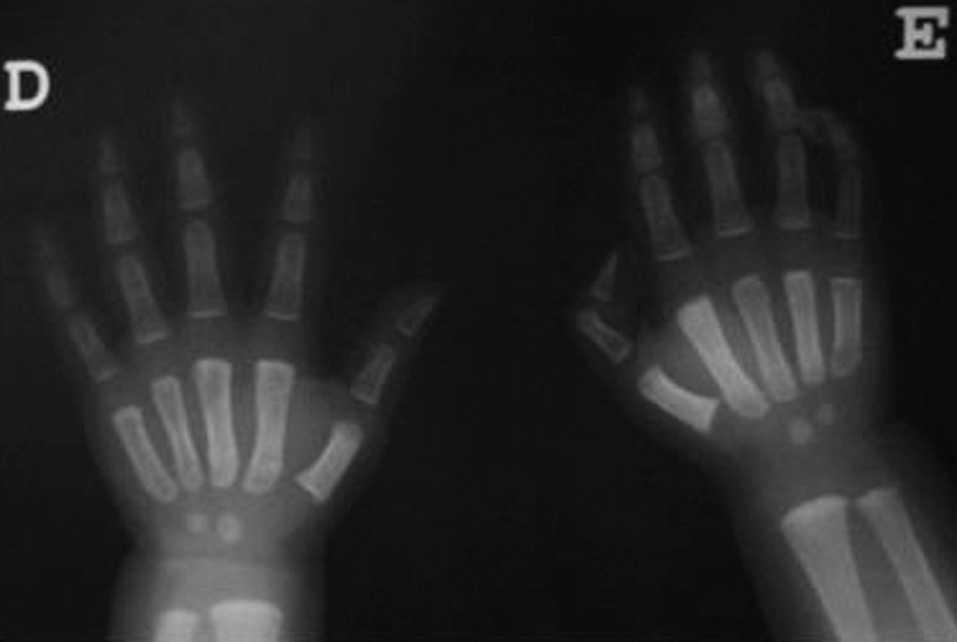

Se practica hemograma en el que se observa anemia normocítica con hemoglobina 8,2 g/dl y hematocrito, 25 %, con aumento de reticulocitos y bilirrubina total, 1,4 mg/dl. La haptoglobina es indetectable, el test de Coombs negativo y las inmunoglobulinas, función hepática y renal, normales. Las serologías a virus de Epstein-Barr, citomegalovirus, virus de la inmunodeficiencia humana y parvovirus B19 y el hemocultivo también resultaron negativos. La radiografía simple mostró edema de partes blandas con discreto refuerzo perióstico en primer metacarpiano (fig. 2).

Figura 2. Radiografía de ambas manos con aumento de partes blandas y refuerzo perióstico en primer metacarpiano de ambas manos.